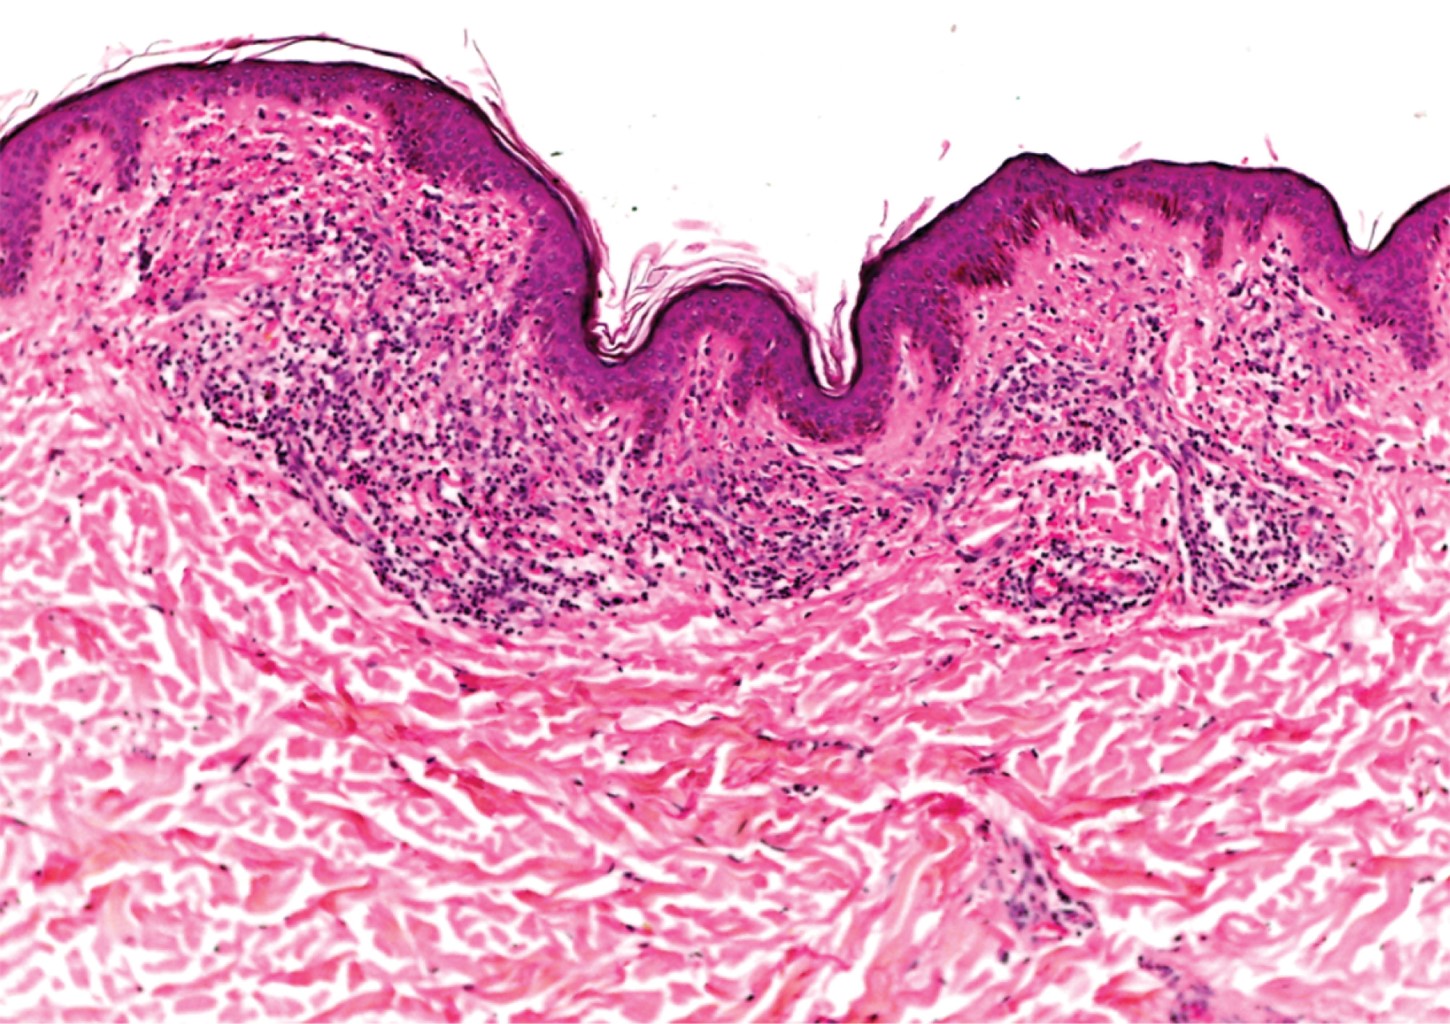

Las imágenes histopatológicas muestran cortes constituidos por múltiples vasos de pequeño calibre de paredes delgadas, dilatados, congestionados, ubicados en la dermis superficial, media, y en menor cantidad en la dermis profunda. No se observan datos de neoangiogénesis.1,7,10

Con el diagnóstico clínico presuntivo de telangiectasia nevoide unilateral versus angioma serpiginoso, se realizó una biopsia incisional de una de las lesiones del hombro. El estudio histopatológico describe una epidermis con escasa capa córnea, aplanamiento de los procesos interpapilares e hiperpigmentación de la capa basal. En dermis superficial se observan vasos dilatados y congestionados, rodeados por infiltrados moderadamente densos, constituidos por linfocitos e histiocitos, además de algunas zonas con extravasación de eritrocitos; resto del corte sin alteraciones (Figuras 4 y 5). Con esto se realiza un diagnóstico histopatológico de dermatitis perivascular superficial con extravasación de eritrocitos, y al realizar correlación clínico-histopatológica se concluye que se trata de un caso de telangiectasia nevoide unilateral adquirida (TNUA). Se solicitan estudios de laboratorio para completar el abordaje (biometría hemática, química sanguínea, perfil de hepatitis viral, prueba de embarazo), todos ellos con resultados dentro de parámetros normales. Se explica ampliamente a la paciente la naturaleza y evolución de su padecimiento. Al ser el dispositivo intrauterino liberador de levonorgestrel el único factor hormonal identificado en la paciente, se sugiere que, en conjunto con el Servicio de Ginecología, se considere cambiar el método de planificación familiar por uno no hormonal. Se da tratamiento con medidas generales.